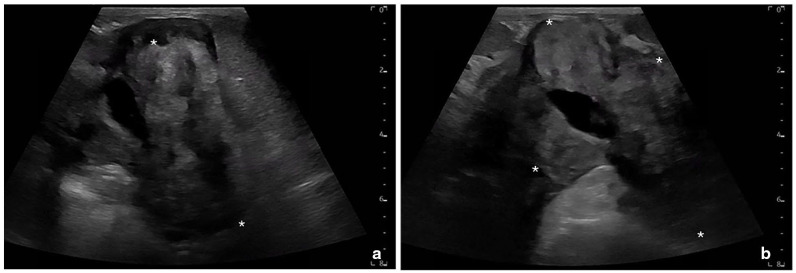

Case summary: A 4-year-old spayed female domestic shorthair cat was presented for evaluation of multiple abdominal masses and hyperglobulinemia. Thoracic radiographs and abdominal ultrasonography revealed a cranial abdominal mass with extension through the aortic hiatus of the diaphragm and into the caudodorsal mediastinum. A diagnosis of feline eosinophilic sclerosing fibroplasia (FESF) with intralesional methicillin-resistant Staphylococcus aureus (MRSA) was obtained based on necropsy results.